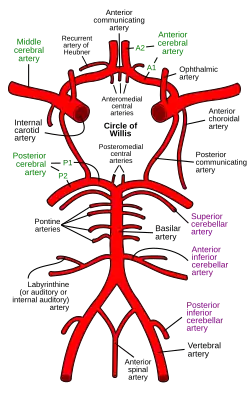

C7: Communicating segment

The communicating segment, or terminal segment, or C7, of the internal carotid artery passes between the optic and oculomotor nerves to the anterior perforated substance at the medial extremity of the lateral cerebral fissure. Angiographically, this segment extends from the origin of the posterior communicating artery to the bifurcation of the internal carotid artery.

The named branches of the communicating segment are:

- the posterior communicating artery

- the anterior choroidal artery

The internal carotid then divides to form the anterior cerebral artery and middle cerebral artery. The circle of Willis provides a collateral pathway for blood supply to the brain.

Circle of Willis

Circle of Willis -

Diagram of the arterial circulation at the base of the brain (inferior view).

Diagram of the arterial circulation at the base of the brain (inferior view).